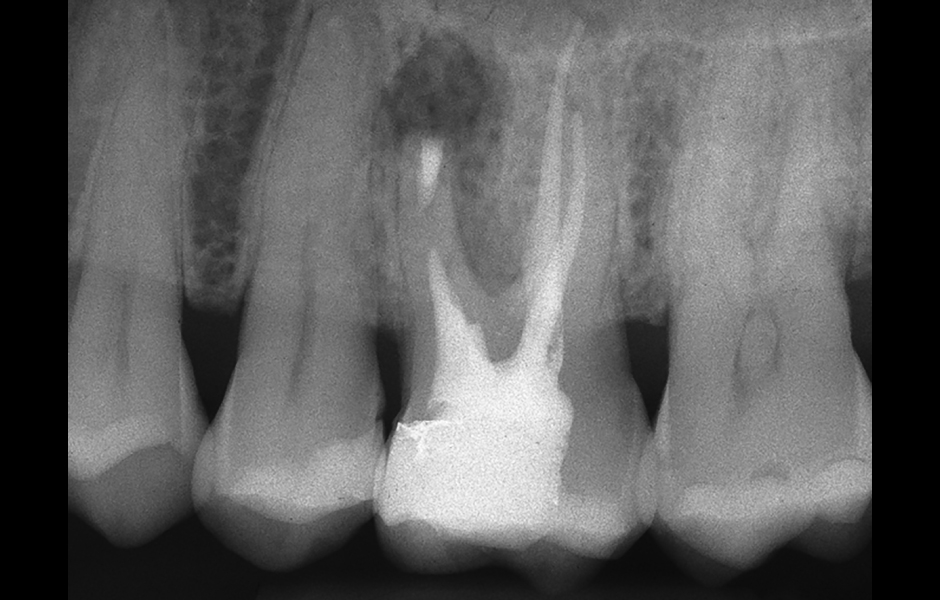

Obr. 1.1: Předoperační rentgenový snímek horního pravého středního řezáku.

Obr. 2.1: Předoperační rentgenový snímek horního pravého druhého moláru. Je patrná drobná laterální radiolucence indikující přítomnost laterálního kanálku.

Obr. 4.1: Předoperační snímek horního levého prvního moláru. Oba kanálky mesiobukálního kořene byly kompletně kalcifikované a nebylo možné je ortográdně zprůchodnit.